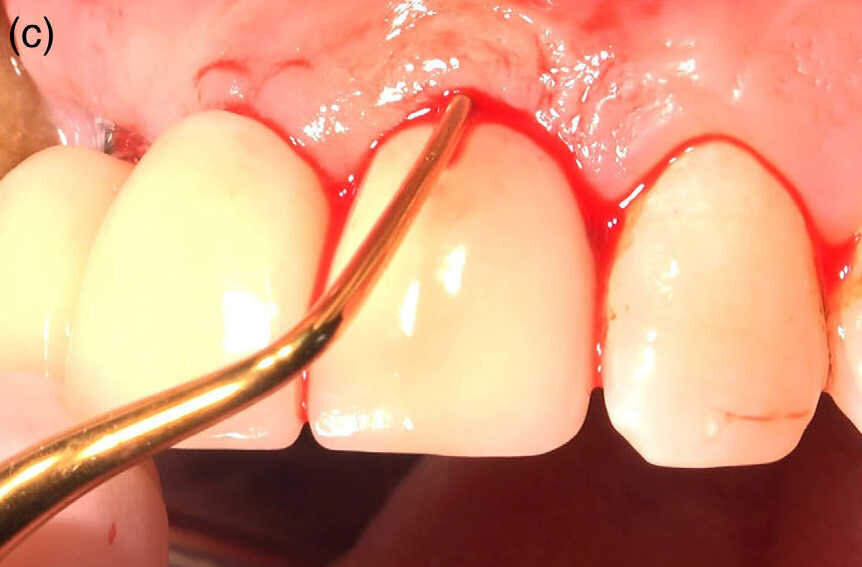

Fig1 (c) : Dégranulation du tissu sans toucher à la surface des implants.